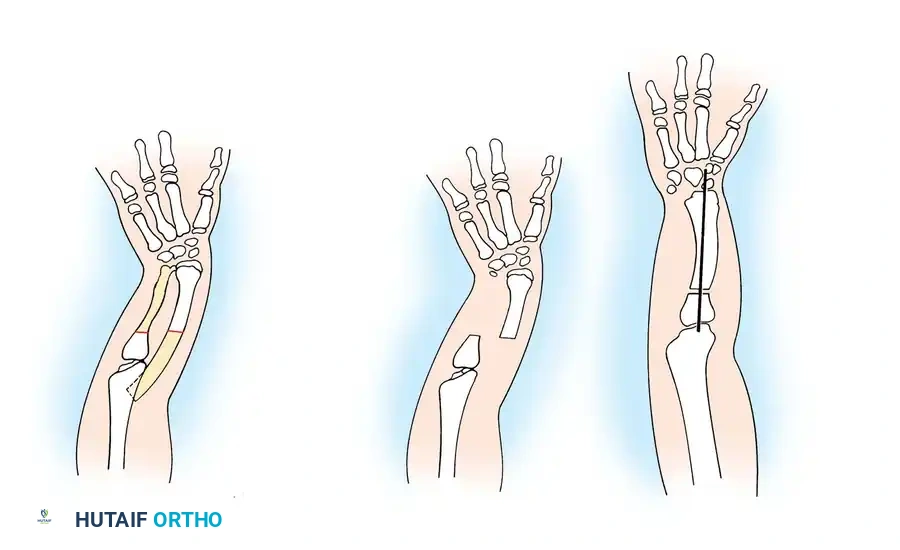

The upper extremity develops between days 26 and 56 of gestation, governed by complex signaling centers including the apical ectodermal ridge and zone of polarizing activity. Disruptions in this embryological sequence can result in transverse deficiencies. Management requires a multidisciplinary approach, prioritizing early prosthetic fitting to match developmental milestones. Surgical interventions, such as the Krukenberg reconstruction, are reserved for specific functional indications, particularly in bilateral amputees with visual impairments.

Surgical Interventions in Transverse Deficiencies

Surgical indications for transverse deficiencies are exceedingly rare. Epps, Burkhalter, and McCollough reported that out of 1,077 children